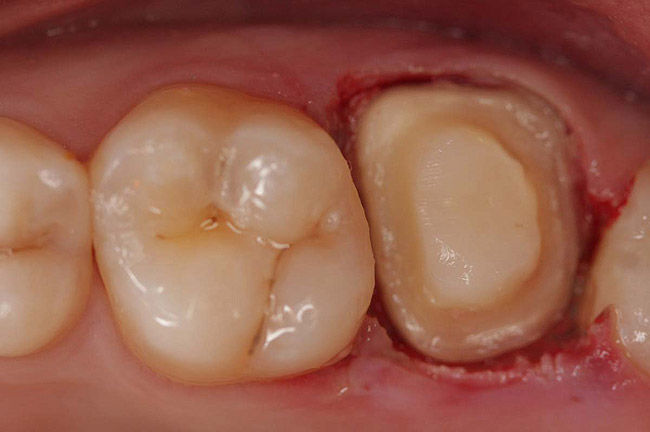

Case 1

A Class IN maxillary bicuspid was previously restored with a fiber post and an all-porcelain crown (Figure 1). The forces of the oral environment resulted in fracture of the fiber post and crown failure. The remaining fiber post in the root was removed, and anti-rotational areas were prepared for a cast post (Figure 2). A gold cast post was constructed at a dental laboratory, using an indirect technique (Figure 3). A porcelain-fused-to-metal (PFM) crown was constructed with a bevel finish to provide a ferrule and reduce forces on the post (Figure 4 and Figure 5).

Figure 6  Endodontically treated maxillary right second molar.

Figure 6

Figure 7  Second molar with the palatal canal prepared for post placement.

Figure 7

Figure 8  Second molar after post cementing.

Figure 8

Figure 9  Cure core material placed without a matrix.

Figure 9

Figure 10  Final tooth preparation to accept a PFM crown.

Figure 10

Figure 11  Final porcelain-fused-to-metal crown.

Figure 11